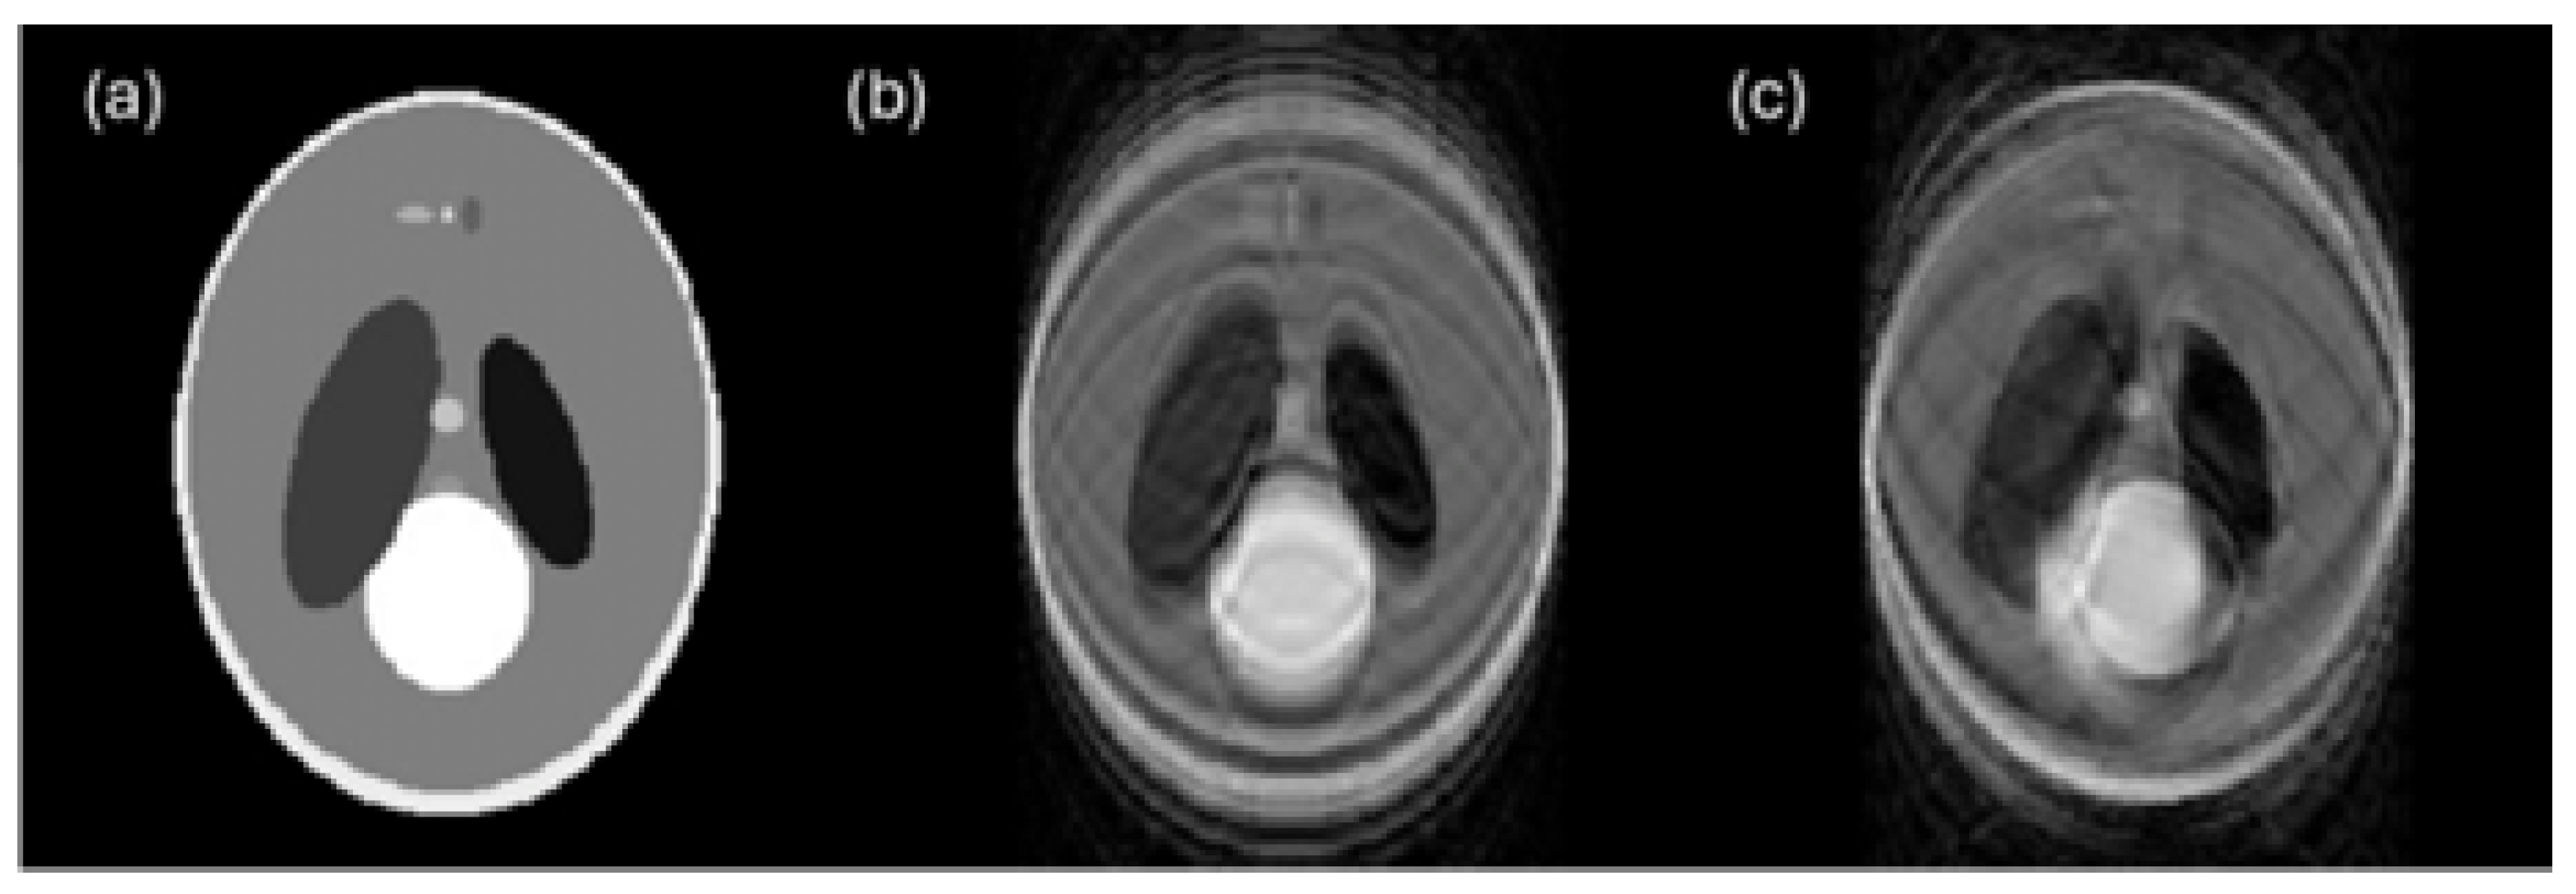

6.2. Beam Hardening Streaks and Cupping Artifacts

6.3. Noise

6.4. Blur